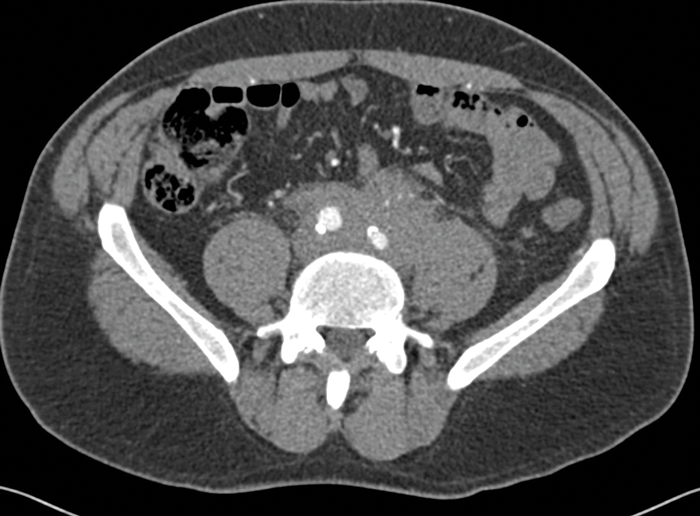

CT is the primary imaging modality used in patients with RPF. It allows evaluation of the location and extent of the fibrosis, as well as assessment for complications including ureteric obstruction or invasion into other vascular structures. CT usually shows an irregular soft tissue mass surrounding the aorta and enveloping the ureters and IVC (Figure 2). The soft tissue has similar Hounsfield units to muscle and the fat plane between the tissue and the psoas may be obliterated.

Figure 2: Arterial phase CT abdomen shows a rim of soft

tissue surrounding the anterior aspect of the aorta.